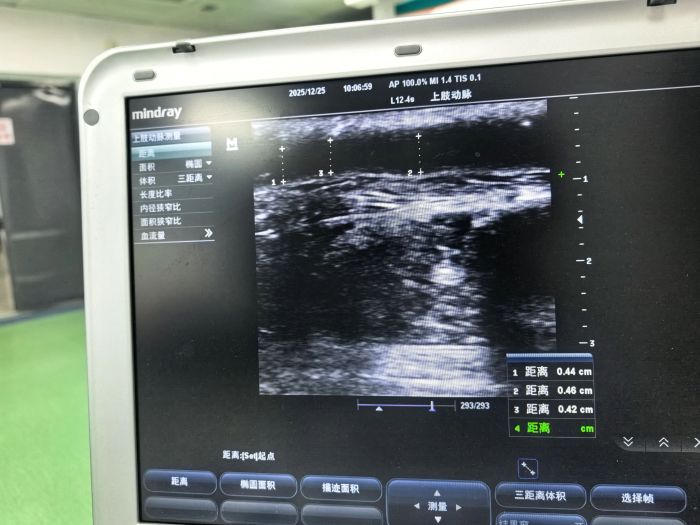

入院后,经血管B超检查提示:头静脉动脉穿刺区狭窄至2mm,狭窄段长达40mm,透析“生命线”濒临阻塞。面对这一危急情况,县人民医院血透团队迅速组建血管通路专项小组,经多学科研判后,决定实施超声引导下PTA术。在征得患者及家属同意后,血透团队在超声实时可视化引导下,通过高压球囊精准扩张狭窄血管,成功将患者狭窄处血管内径扩张至4-5mm,头静脉血流即刻恢复通畅。